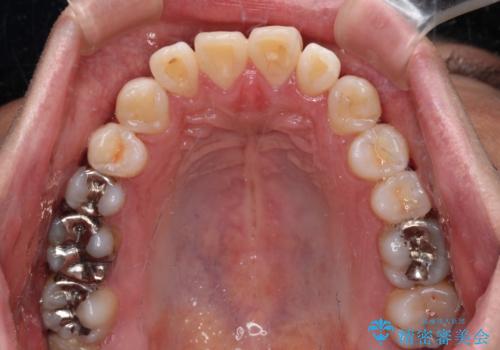

- 治療計画

精密検査の結果、上下左右の小臼歯4本を抜歯し、そのスペースに前歯を後方へ移動させる矯正治療をご提案しました。

治療期間は約2年。

少しずつ前歯を後ろに下げていくことで、横顔のラインが整い、口元の“出っ張り感”が解消。

治療後には「自然に笑えるようになった」と嬉しいお声をいただきました。